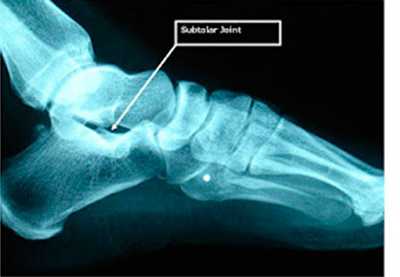

Рис. 3. Рентгенограмма подтаранного сустава